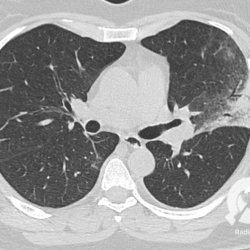

Os agentes etiológicos infecciosos são variados (bactérias, vírus, fungos, parasitas…), mas o que ocorre nos pulmões durante uma infecção por qualquer tipo de agente é a substituição do ar alveolar por secreção (pus, muco, eventualmente sangue ou necrose…) e com isso a manifestação radiográfica vai ser a mesma já que todas estas secreções apresentam a mesma densidade radiográfica: partes moles.

E o nome dado a esta alteração radiográfica que corresponde à substituição do ar alveolar por líquido é a consolidação alveolar.

Uma consolidação alveolar é, por definição, uma opacidade (imagem densa, branquinha) homogênea ou às vezes heterogênea (pela presença de calcificações ou cavidades), de limites mal definidos, exceto quando toca a pleura da parede ou das cissuras pulmonares. É um termo usado tanto em radiografia, como em tomografia computadorizada. Na tomografia, um outro termo é usado: vidro fosco, que é uma opacidade (branquinha mas não tanto como a consolidação), que borra o pulmão mas deixa ver os vasos de permeio (igual bigode de adolescente: dá pra ver todo o fundo).

Nós vamos mostrar aqui um pequeno apanhado de pneumonias de variados agentes, em diversos segmentos e lobos pulmonares, com extensões variadas. O objetivo é identificar o padrão radiológico de consolidação alveolar e não determinar o agente infeccioso, isso vai ser assunto para mais adiante. Aliás já antecipo que é fundamental saber localizar a lesão, porque alguns destes bichos gostam de determinados segmentos, alguns tumores também têm as suas preferências, então localização é fundamental. Se localização não fosse importante, um apartamento na beira do mar sairia o mesmo preço de um apartamento de frente pra BR-101, concordam?